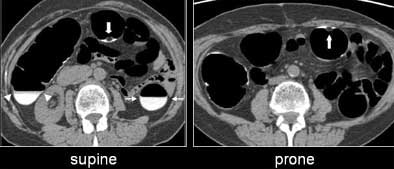

![]() |

| Untagged stool can be seen floating in a small pool of barium (large white arrow, right and left). Well-tagged fluid in the descending (small white arrows) and the ascending (white arrowheads) colon. All images courtesy of Dr. Hiro Yoshida. |